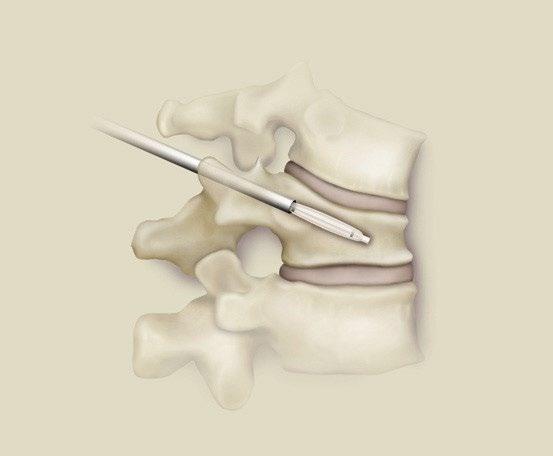

Local Therapy

Kasperk 2012 J Surg Oncol